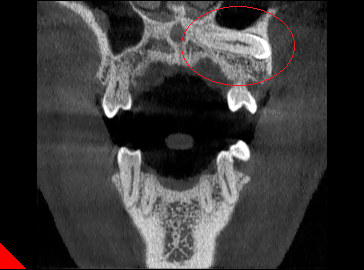

◆埋伏牙

◆牙瘤

◆由囊肿引起的骨质破坏